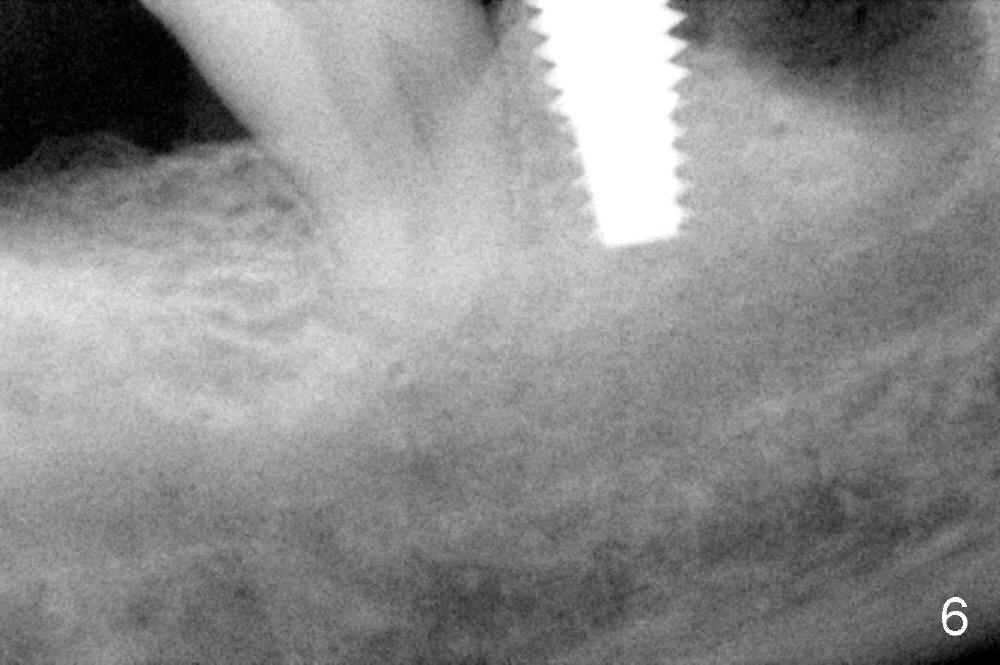

As to where to place an implant, we try to engage the largest tap (8 mm in diameter) into the mesial socket without binding. The buccal plate of the mesial socket is missing. It is risky to extend osteotomy in the mesial socket. Besides, the septum (Fig. 4 S) is not as tall as the distal socket (D). It appears that the distal socket is the safest place to place an implant. Furthermore, no drill is used for distal osteotomy. Instead two osteotomes (3.5x15 and 4x15 mm tapered osteotomes) are used to expand the distal socket with intention to push the septum mesially. Since the bone density is high, the osteotomes seem not to work as effectively as expected. Then a 4.5x17 mm tap is placed at the depth ~ 14 mm with stability (Fig.5). Finally a 5x14 mm tissue-level implant is placed with insertion torque >60 Ncm (Fig.6). Allograft is placed in the mesial socket and buccal aspect of the distal socket, followed by insertion of collagen plug and membrane (Fig.7). After insertion of an abutment (Fig.8 (taken 6 days postop) *), perio dressing (P) is applied to cover the wound. There is no postop paresthesia.